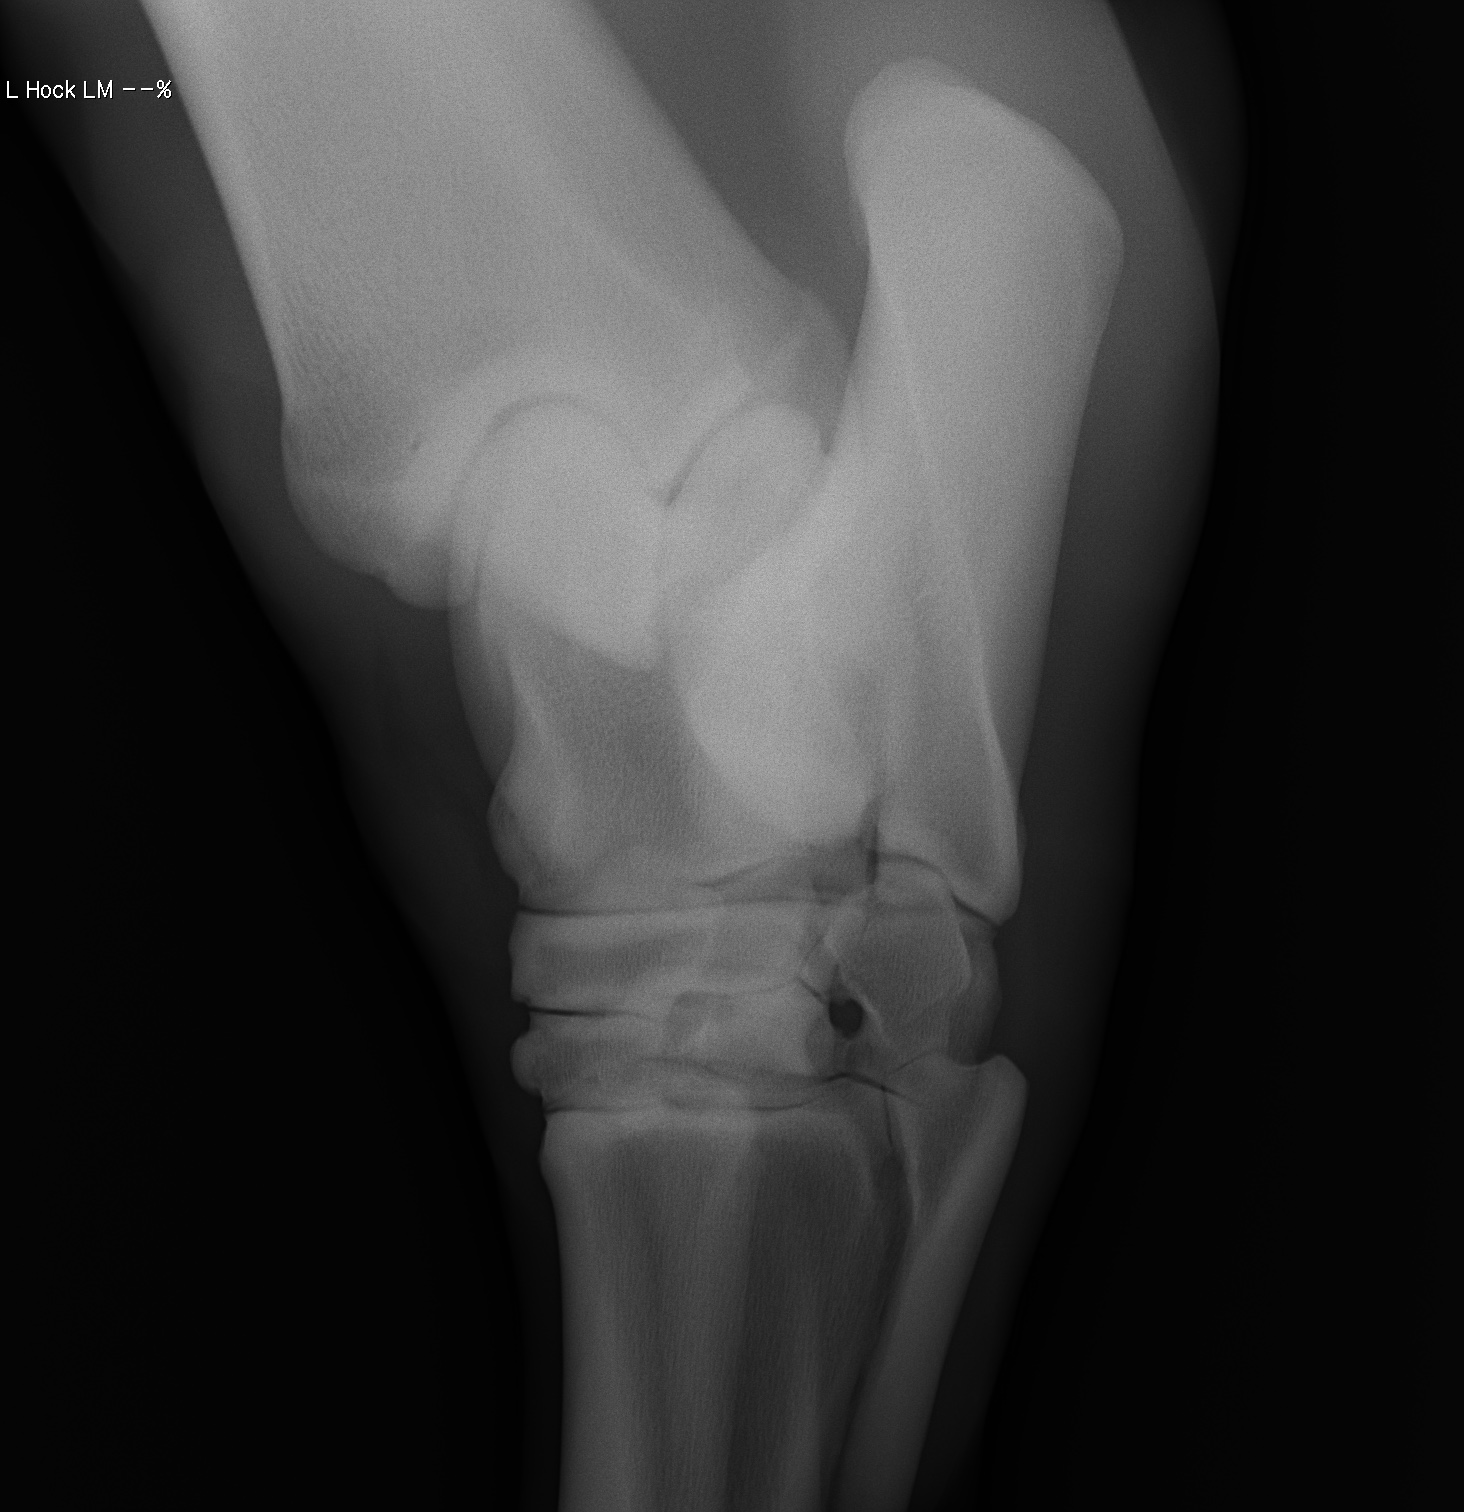

添付のレントゲン画像をご確認ください。現状渡しのノークレームノーリターンでお願いいたします。記載事項に関するキャンセルには応じられません。

※2022年12月17日の競走にて左後脛骨不全骨折を発症しています(全治6~9ヵ月)。